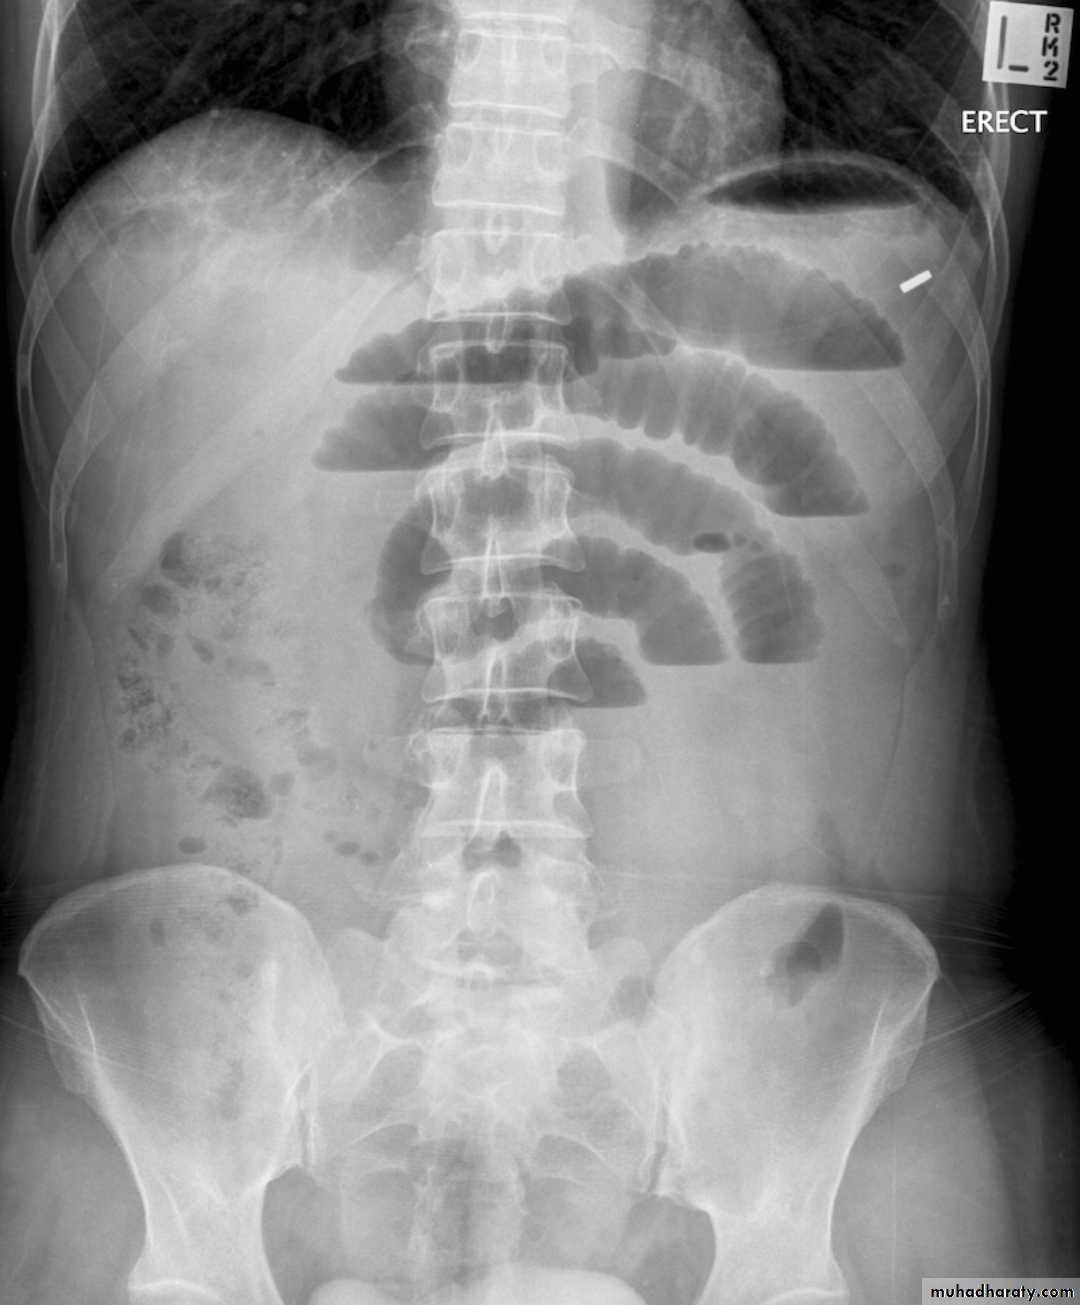

Small bowel obstruction accounts for 80% all mechanical intestinal obstruction; the remaining 20% result from large bowel obstruction

Radiographic features

Abdominal radiograph

Abdominal radiographs are only 50-60% sensitive for small bowel obstruction .

In most cases, the abdominal radiograph will have the following features:

dilated loops of small bowel proximal to the obstruction

predominantly central dilated loops

three instances of dilatation over 3 cm

valvulae conniventes are visible

fluid levels if the study in erect position